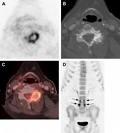

May 14, 2009 -On May 8, 2009, CMS opened the reconsideration of the National Coverage Determination (NCD) on Positron Emission Tomography (FDG). The requestors have asked CMS to reconsider the NCD and broaden national coverage of FDG-PET (without CED restrictions) for the staging of cervical cancer (i.e. in those women who have been diagnosed with cervical cancer but who do not otherwise meet the coverage criteria). The requestors also ask that the use of FDG-PET be nationally noncovered to make the diagnosis of cervical cancer, as this imaging is not helpful to make the initial diagnosis.

Currently, Medicare covers, nationally, FDG-PET when it is used by the beneficiary’s physician to guide the subsequent management of cervical cancer in women who have undergone anticancer treatment. For example, FDG-PET is covered to determine whether or not the cancer has responded to treatment or to determine if the patient's symptoms are being caused by a recurrence or spreading of the cancer.

Additionally, FDG-PET is nationally covered for some uses in women diagnosed with cervical cancer who have not yet received anticancer treatment. Specifically, FDG-PET imaging is covered as an adjunct test for the detection of pre-treatment metastasis (i.e., staging) in newly diagnosed cervical cancers following conventional imaging that is negative for extra-pelvic metastasis.